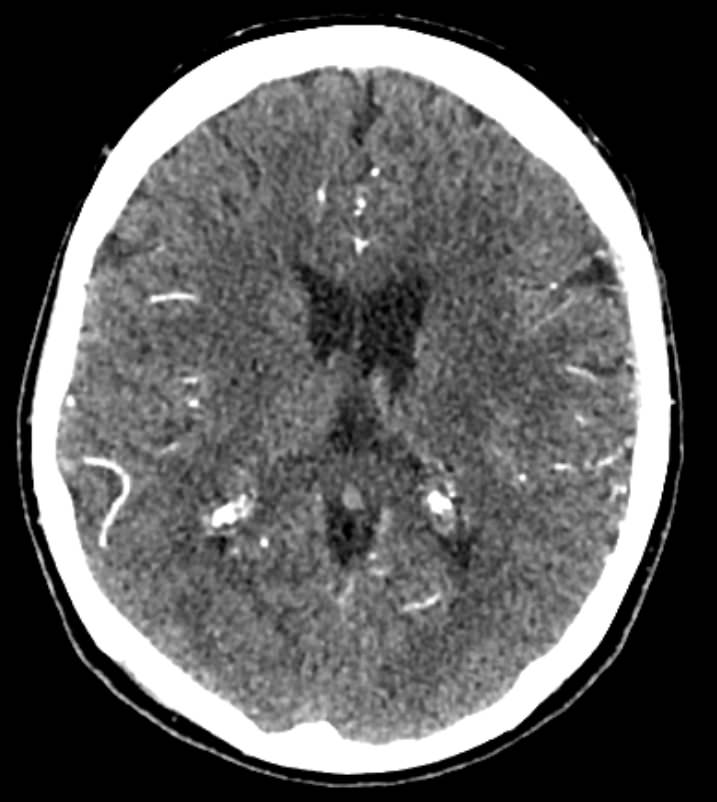

Мультиспиральная компьютерная томография сосудов головного мозга (КТ-ангиография) относится к лучевым методам исследования и применяется для оценки состояния сосудистого русла головного мозга. КТ-ангиография основана на применении рентгеновского излучения, при этом обязательно проводится контрастирование сосудов головного мозга.

Процедура заключается в том, что трубка томографа вращается вокруг анатомической зоны исследования и с помощью рентгеновских лучей делает послойные снимки, которые затем реконструируются в трехмерные изображения сосудистой системы в мельчайших подробностях. При этом по сравнению с классической ангиографией компьютерная томография не требует вмешательства в организм пациента и проводится в амбулаторных условиях.

Высокая диагностическая информативность КТ-ангиографии в сочетании с быстротой и неинвазивностью делают эту процедуру безопасной и эффективной методикой обследования сосудов головного мозга у пациентов с неврологической симптоматикой. Но особенную ценность КТ сосудов головного мозга имеет в плане скринингового обследования. Это позволяет выявлять аневризмы (расширение стенки артерии), патологическую извитость, аномалии развитии (артериовенозные мальформации), сужения просвета сосудов за счет атеросклеротических бляшек или экстравазальной, например вертеброгенной, компрессии и другие серьезные заболевания, которые долгое время могут протекать бессимптомно.

КТ-ангиография головного мозга в нашей клинике проводится на современных мультиспиральных компьютерных томографах последнего поколения TOSHIBA AQUILION. Благодаря инновационным компьютерным программам получаются детализированные снимки высокого качества и 3D-модели сосудистой системы головного мозга. При этом аппараты обеспечивают пониженный уровень лучевой нагрузки на организм пациента.

Для лучшей визуализации сосудов в обязательном порядке в вену пациента вводится йодсодержащий контрастный препарат. Контрастное вещество поглощает рентгеновские лучи, поэтому даже мелкие сосуды становятся хорошо видны на фоне окружающих тканей.